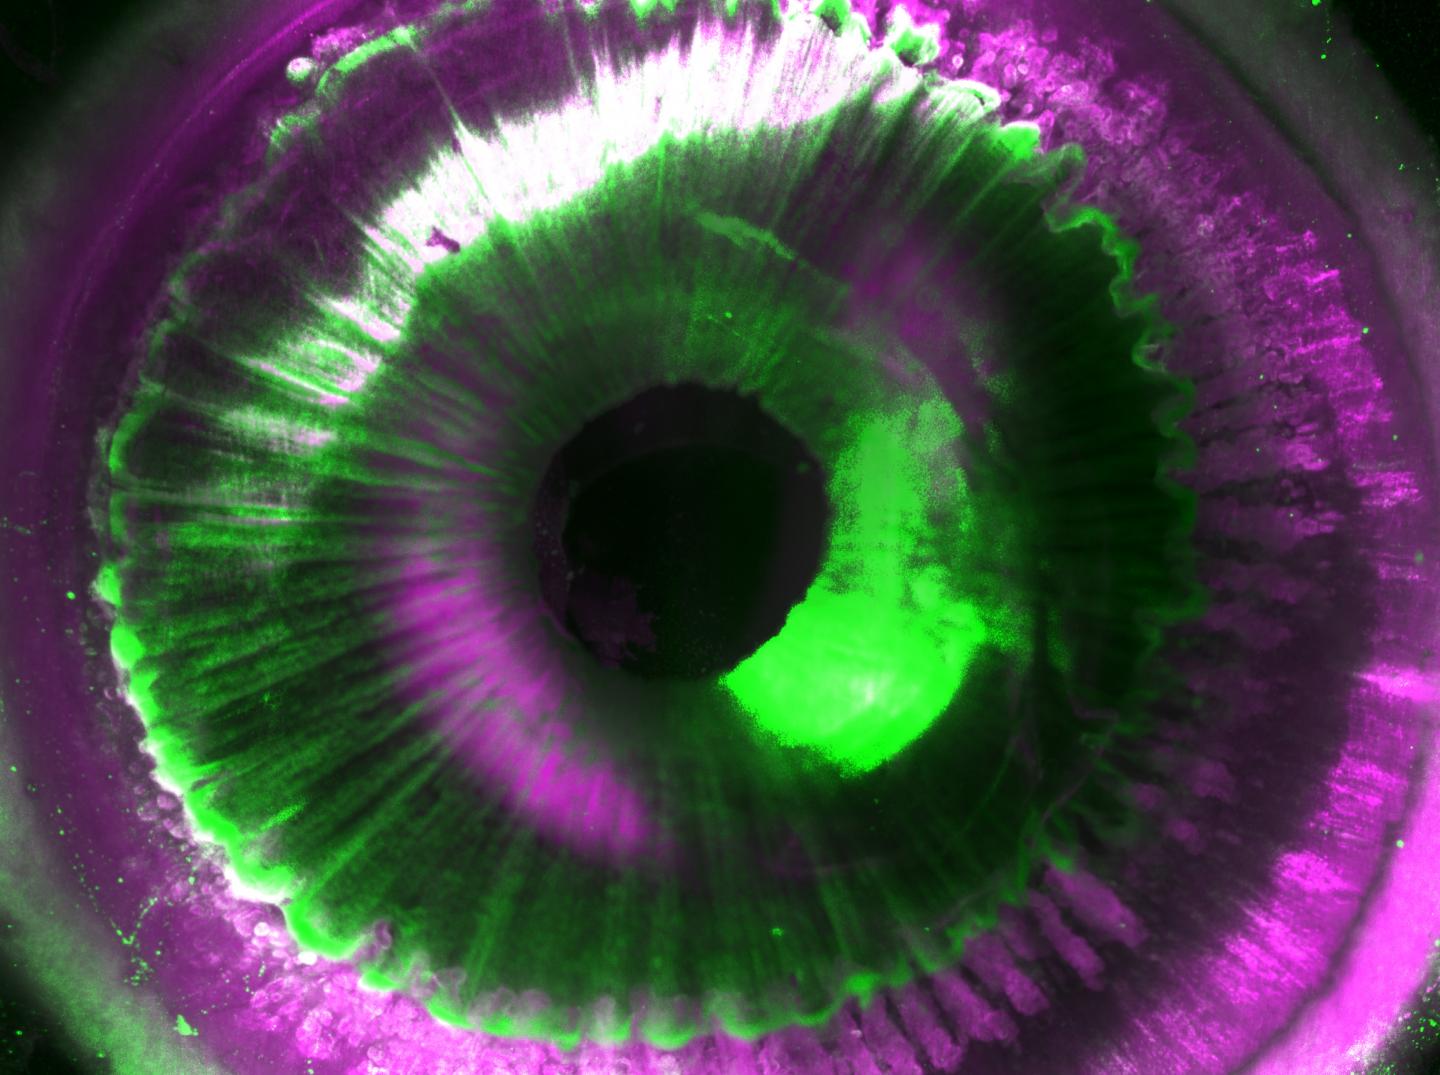

For the first time, researchers managed to make intact human organs transparent. Using microscopic imaging they could revealed underlying complex structures of the see-through organs at the cellular level. Resulting organ maps can serve as templates for 3D-bioprinting technologies. In the future, this could lead to the creation of on demand artificial organs for many patients in need. The findings published in Cell joined forces from Helmholtz Zentrum München, Ludwig Maximilians University Munich (LMU), and Technical University of Munich (TUM).

In biomedical research, seeing is believing. Deciphering the structural complexity of human organs has always been a major challenge due to the lack of technologies to image them at the cellular level. Recent developments in tissue clearing allowed researchers to obtain first cellular views of intact transparent mouse organs in 3D. These methods, however, were not applicable to human organs.

After making the human organs transparent, which were obtained post mortem from Prof. Ingo Bechmann's lab at the University of Leipzig, the team had to tackle additional challenges for both organ imaging and the analysis of the large amount of resulting data. First, they developed a new laser-scanning microscope with a large sample holding capacity called "Ultramicroscope Blaze" in collaboration with Miltenyi Biotec. This microscope enabled imaging of human organs as large as the kidney. Next, together with Prof. Bjoern Menze from TUM, the team developed deep learning algorithms to be able to analyze hundreds of millions of cells in 3D.

The researchers named this new technology SHANEL (Small-micelle-mediated Human orgAN Efficient clearing and Labeling). "SHANEL can develop into a key technology for mapping intact human organs in the near future. This would dramatically accelerate our understanding of organs such as the brain, their development and function in health and disease," explains Dr. Ali Ertürk, Director of the Institute for Tissue Engineering and Regenerative Medicine at Helmholtz Zentrum München and also Principal Investigator at the Institute for Stroke and Dementia Research at the hospital of LMU.